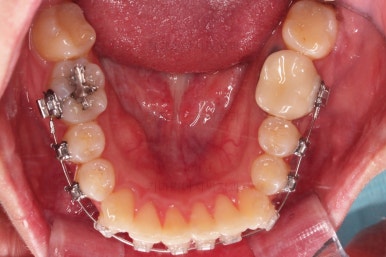

초진 시 입안의 모습입니다.

전반적으로 치열이 삐뚤고, 특정 앞니는 톡 튀어나가 미적으로 좋지 못한 상황이었습니다.

이갈이, 이악물기 습관도 있어서 앞니는 삐뚤어진 채로 치아가 많이 갈려있는 상황이었습니다.